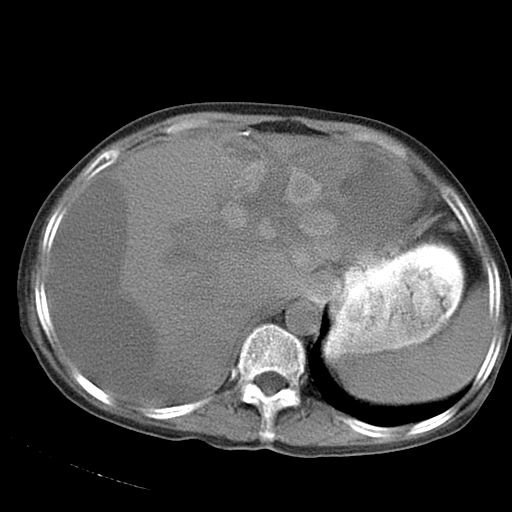

以下是引用dyqct在2006-12-7 21:08:00的发言:[br]考虑:1、肝内外胆管多发性结石伴肝左叶外侧段肝萎缩;[br] 2、右膈下多发脓肿;[br] 3、右侧少量胸腔积液、斜裂积液;[br] 4、左肾囊肿。

以下是引用jiazh在2006-12-7 20:37:00的发言:[br]肝脏周围半狐形低密度影,肝脏表面受压推移,考虑膈下脓肿可能性大;2、右侧胸腔积液

以下是引用拾荒者在2006-12-7 21:44:00的发言:[br]肝内外胆管多发结石,右膈下多发脓肿,右胸膜腔及叶间裂积液,左肾囊肿。[br] [br]